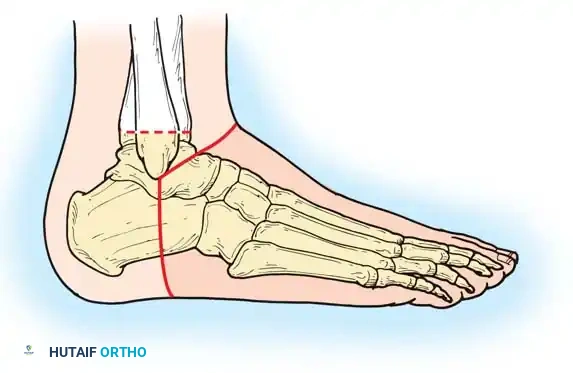

- Place the patient supine. A single, long posterior heel flap is utilized.

- Begin the incision at the distal tip of the lateral malleolus. Pass it across the anterior aspect of the ankle joint at the level of the distal tibia to a point exactly one fingerbreadth inferior to the tip of the medial malleolus.

- Extend the incision directly plantarward, across the sole of the foot to the lateral aspect, ending at the starting point.

Step 4: Bone Transection

- Retract the heel flap posteriorly. Dissect the soft tissue from the tibia and malleoli.

- Incise the periosteum circumferentially 0.6 cm proximal to the joint line.

- Using an oscillating saw, divide the tibia and fibula at this level. The line of transection must pass just through the dome of the ankle joint centrally.

- Alignment: The plane of the transection must be perfectly parallel to the ground when the patient is standing. Round and smooth all sharp cortical edges with a rasp.